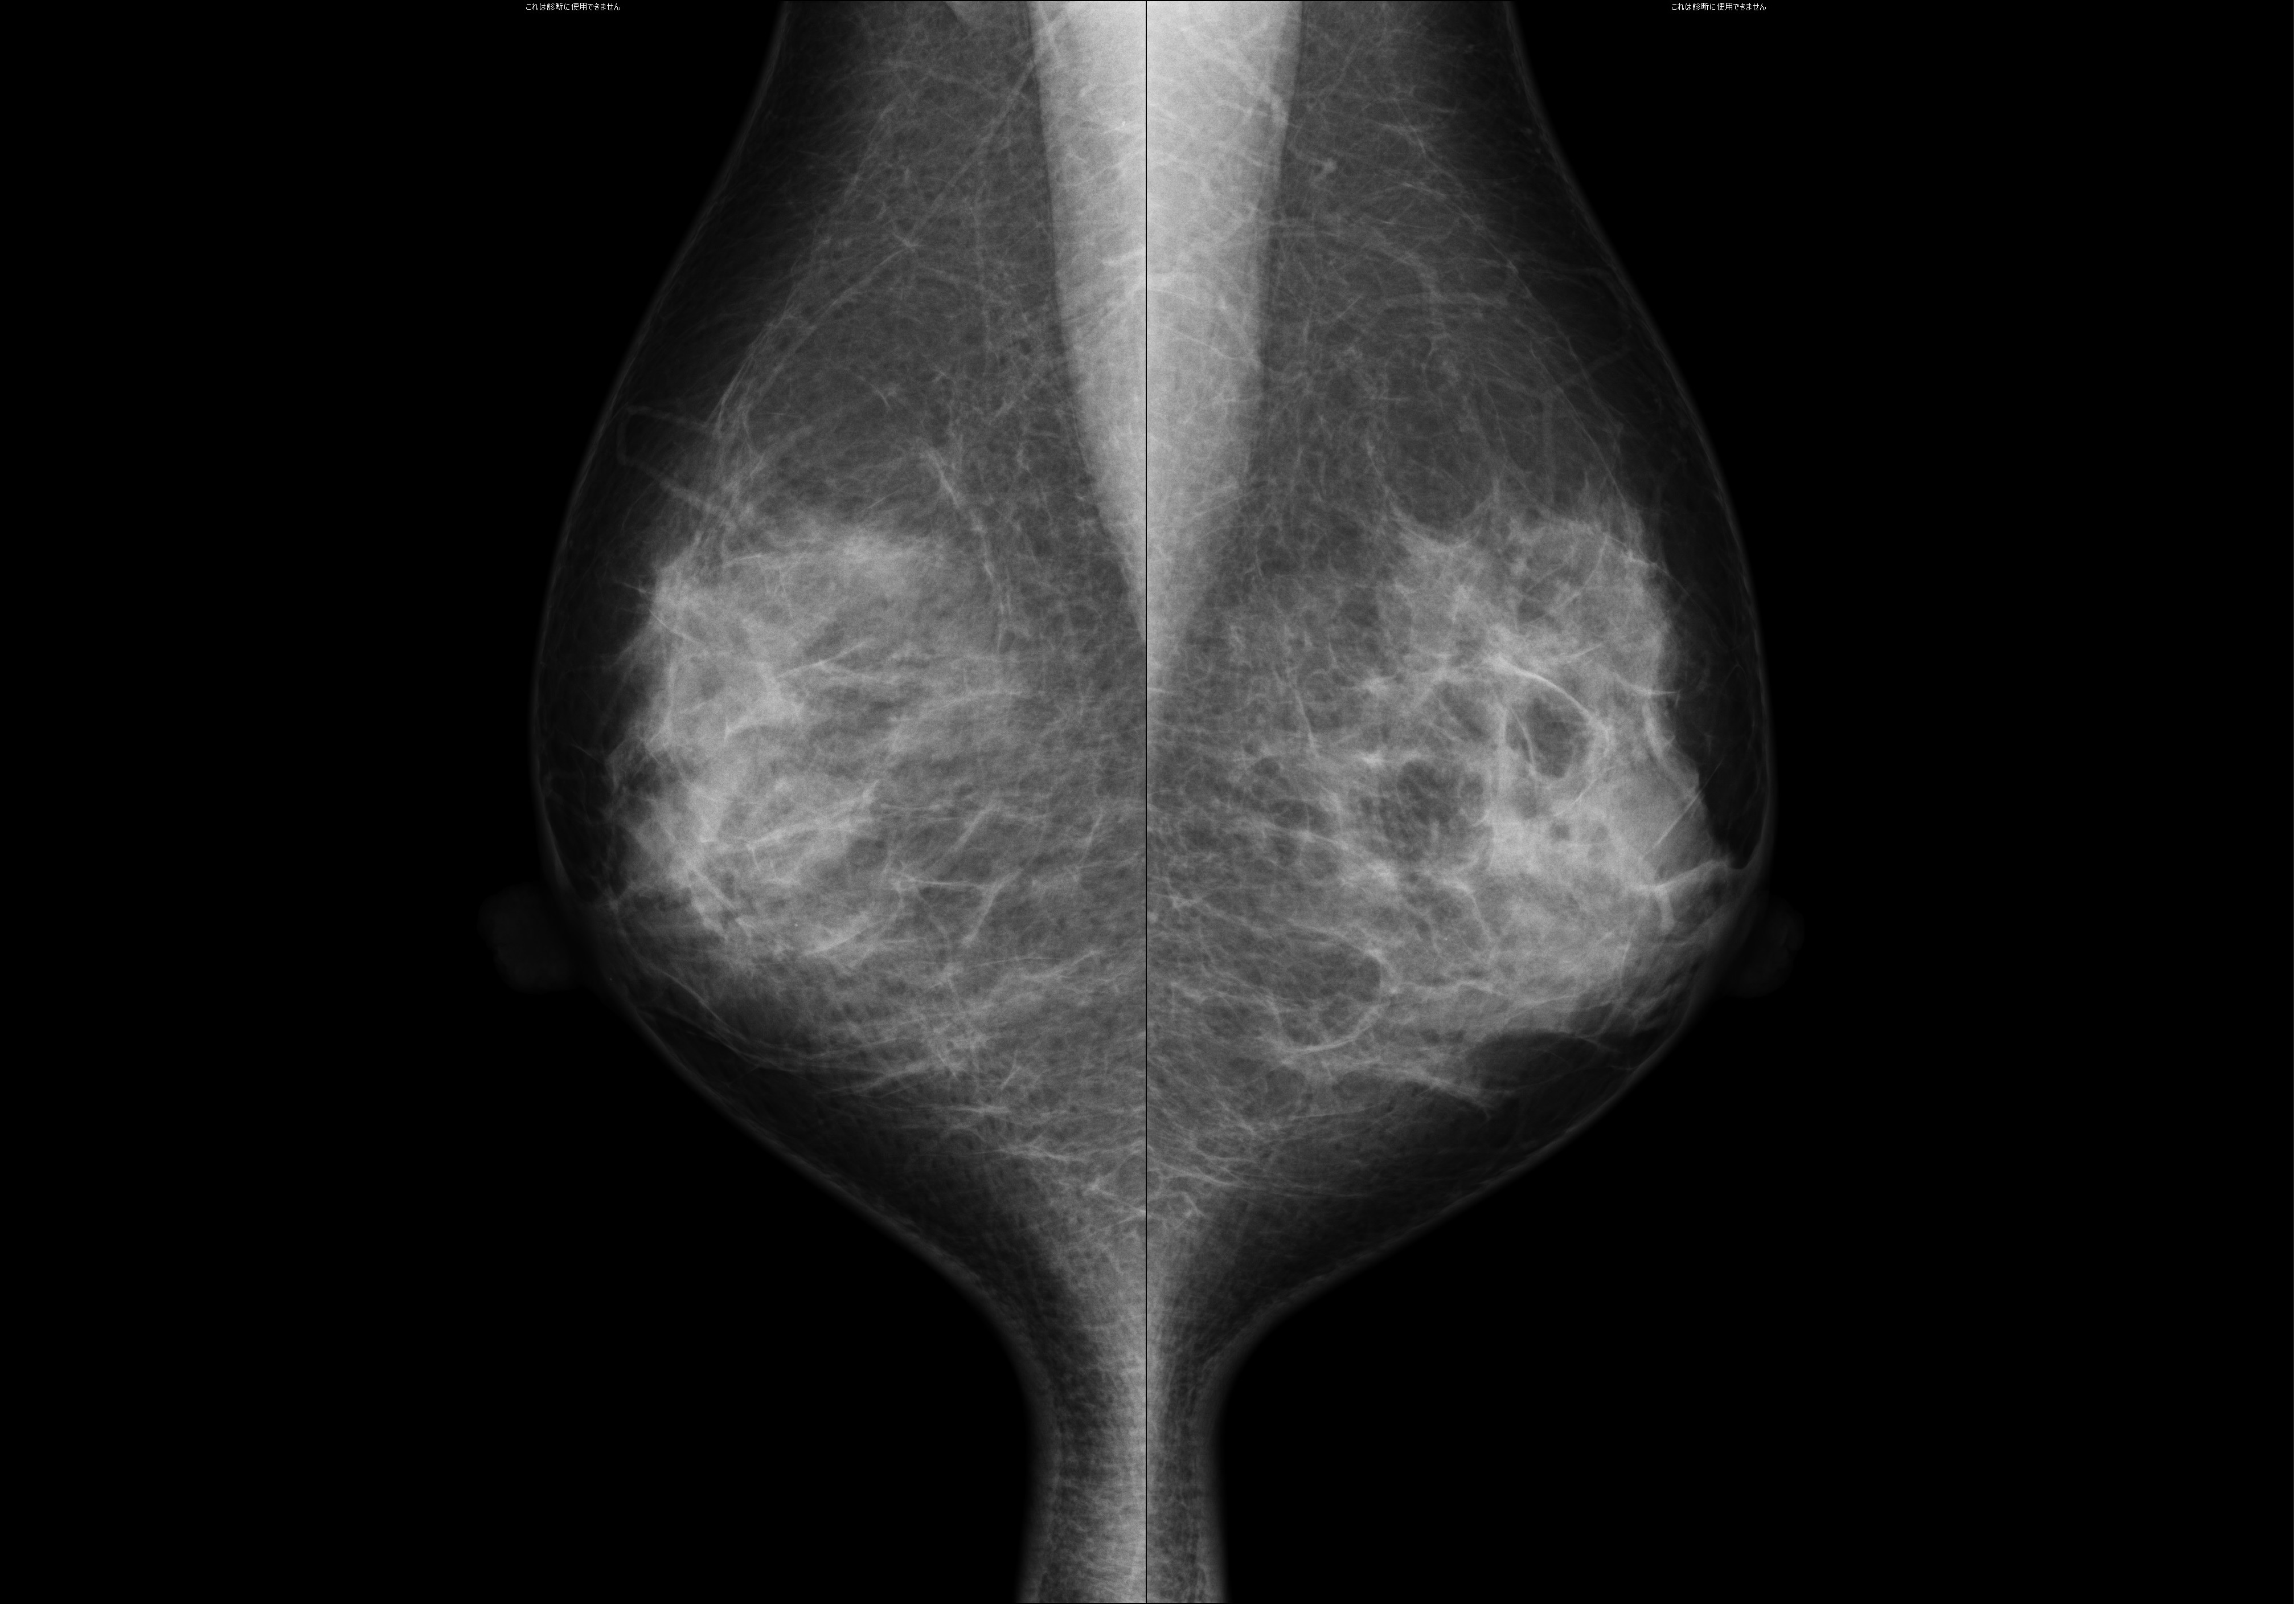

マンモグラフィとは乳房専用のレントゲン検査です。

触診で見つけることのできないような早期の乳がんを発見するのに非常に有効です。

乳房は柔らかい組織でできているため専用の装置を使用します。圧迫板で上下方向・左右方向から乳房をはさみ薄く伸ばすことで、がんと正常組織の区別をつきやすくして撮影しています。

当院はNPO法人日本乳がん検診精度管理中央機構によって定められた検診精度管理の線量・画像基準を満たすマンモグラフィ検診施設として認定されており、撮影は女性技師のみで行っています。

乳がん検診の基本であるマンモグラフィは濃度の高い乳房では感度がおちることが知られています。

超音波検査は高濃度乳房が多い日本人女性に向いている検査と言えます。また、マンモグラフィ不適とされた乳房、胸郭に異常のある方、ペースメーカー、除細動器挿入後の方にも適した検査です。